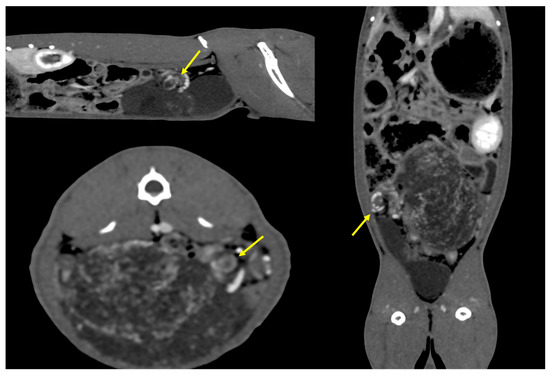

2. Clinical Case